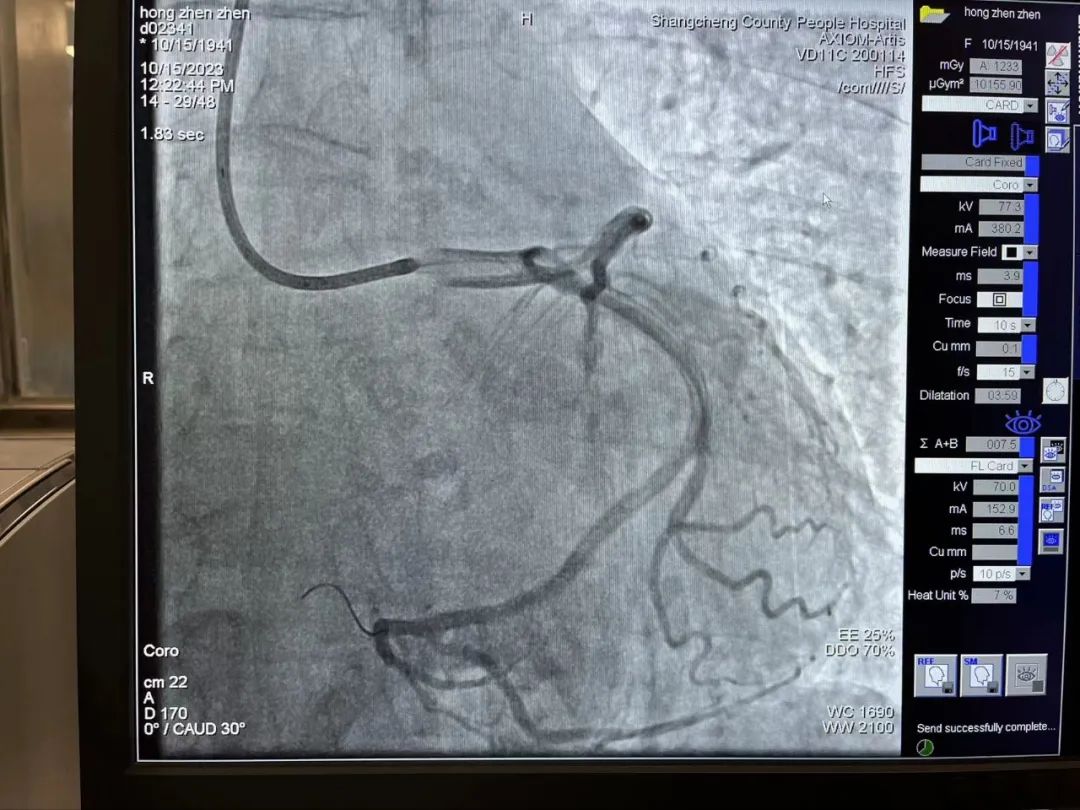

然而,患者急诊冠状造影结果显示:左右冠脉主干血管未见明显狭窄,无法确定“罪犯血管”,但是患者心电图提示下壁仍然持续抬高,胸痛症状得不到缓解,病情扑朔迷离。一直在导管室指导的熊晨晖主任仔细观察了影像结果,发现患者右冠细小,回旋支远端可为右心供血,可能为“功能性右冠脉”,所以考虑回旋支远端为“罪犯血管”。随即邀请郑州大学第一附属医院心内科教授远程会诊,教授同意熊主任的观点,认为左旋支可能是“罪犯血管”,但认为回旋支远端较细、且供血区域局限,介入手术治疗获益不能肯定,可以尝试手术看看效果,也可以先药物治疗。

2023-10-19_勇攀“心”高峰——记商城县人民医院心血管内科介入能力再突破!_6.jpg

右冠脉细小,未见明显狭窄